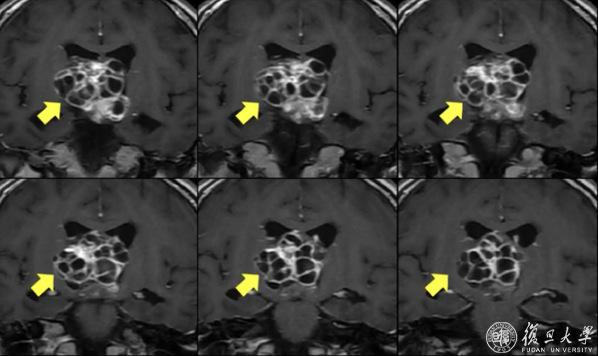

且不说它内含的十几个“魔眼”般狰狞的囊肿,像榴籽一样相互包裹、挤压,直插大脑核心区;单就它的大小,直径超过4厘米,挤满整个脑深部的中央区域,也是闻所未闻,国内外文献罕见有过这个位置这么大肿瘤的报道。

术前核磁共振显示脑深部巨大肿瘤,压迫下丘脑和脑干